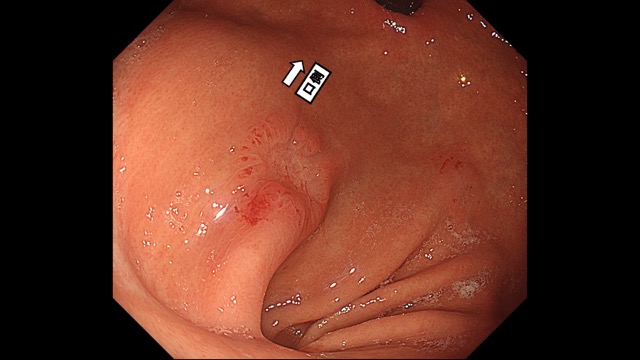

胃012